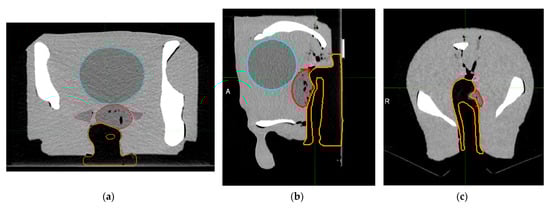

3.3. Dose Distributions